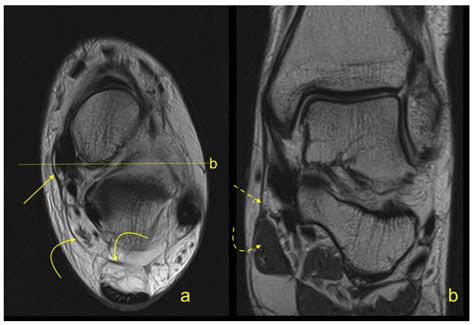

To diagnose issues related to the flexor retinaculum, medical professionals typically perform a physical examination. The Tinel’s sign test—tapping over the area of the retinaculum to elicit tingling in the foot—is a standard diagnostic indicator. Imaging studies such as Ultrasound or MRI are frequently used to visualize the thickness of the retinaculum and identify any cysts, scar tissue, or anatomical variations that may be contributing to nerve compression.